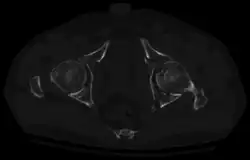

Axial CT image (viewed on bone windows) of a complex comminuted left acetabular fracture involving both anterior and posterior columns. -

Fracture of the acetabulum